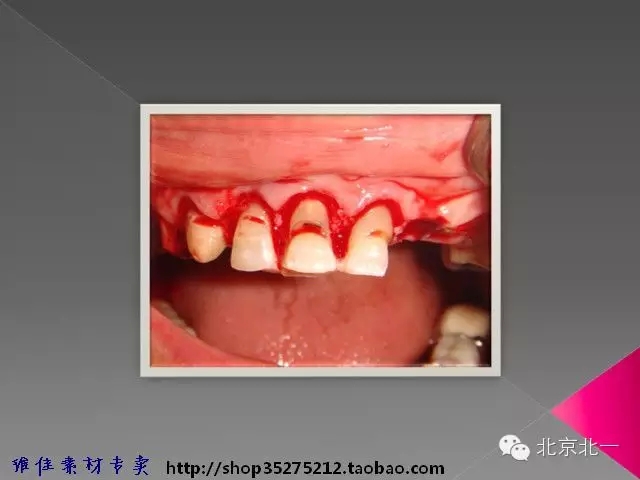

【牙周學(xué)習(xí)】冠延長手術(shù)